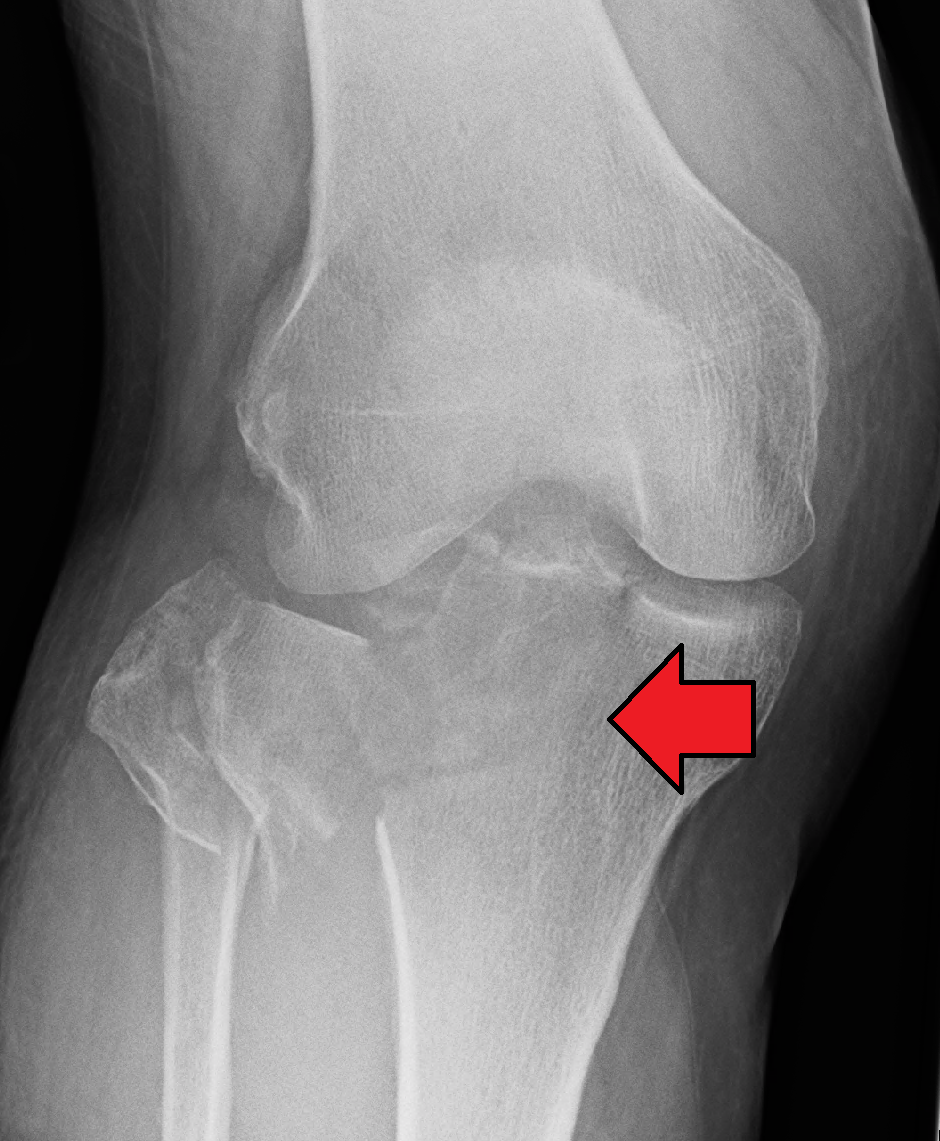

Fractura impactata - frecvent intalnita in

A

osul metafizar

fracturi col femural

extremitate distala radiala

platou tibial